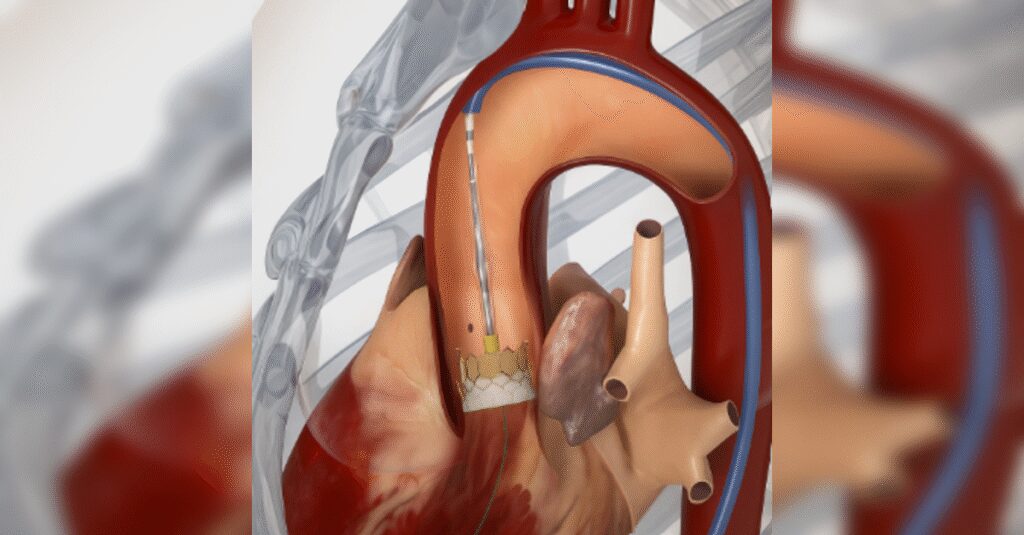

Mumbai: Edwards Lifesciences, a global leader in structural heart innovations, has announced the launch of its next-generation transcatheter heart valve platform in India, marking a significant milestone in the treatment of aortic stenosis.

This advanced therapy is designed to meet the needs of patients who are not candidates for open-heart surgery, offering a durable, minimally invasive solution that supports long-term health and quality of life.

Edwards’ latest-generation balloon-expandable transcatheter heart valve incorporates a proprietary calcification-resistant tissue technology that helps prevent calcium buildup on the valve leaflets, which is a primary cause of structural valve deterioration and the need for reintervention. The valve also features dry tissue storage, simplifying hospital workflows, and a taller, textured outer sealing skirt to reduce paravalvular leak.4,5

Central to Edwards’ approach is its ‘lifetime management’ principle, which prioritises comprehensive planning of a patient’s treatment journey from the initial procedure. A key component is the valve-in-valve technique, which enables the placement of a new transcatheter valve within an existing transcatheter valve or a degenerated surgical valve, should degeneration occur years later. This approach maintains a minimally invasive pathway and reduces the need for repeat open-heart surgery in patients requiring future interventions.Commenting on the Edwards’ next-generation transcatheter heart valve platform, reputed cardiologists from India shared their perspectives. Dr. Ravinder Singh Rao, Interventional Cardiologist, Lilavati Hospital Mumbai said, “The newer transcatheter heart valve, which is more durable and long-lasting, will allow us to safely and effectively treat younger patients with severe aortic stenosis.”